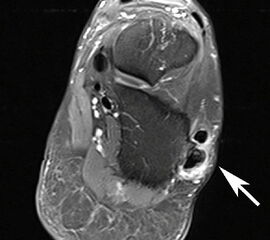

MRT mit KM bei Split der Peronaeus brevis Sehne in Höhe der Fibulaspitze

Abbildung 13

Klassischerweise beginnt eine Peronealsehnenruptur mit einem Distorsionstrauma. Bei dieser Verletzung kommt es zunächst zu einer Längsruptur (Peroneus-Split) der Peronaeus brevis Sehne in Höhe der Fibulaspitze. Bestehen nun Risikofaktoren wie eine persistierende Instabilität des Sprunggelenks oder ein bis zu diesem Zeitpunkt asymptomatischer Rückfußvarus, kommt bei jeder weiteren Distorsion zu einer Zunahme des Sehnenschadens bis hin zur vollständigen Kontinuitätsunterbrechung 38. Für das Peronaeus Split Syndrom gibt es kein klassisches Leitsymptom. Wichtig ist bei anhaltenden Beschwerden nach einem Distorsionstrauma an diese Differentialdiagnose zu denken und ein MRT mit Kontrastmittel zu veranlassen 39.